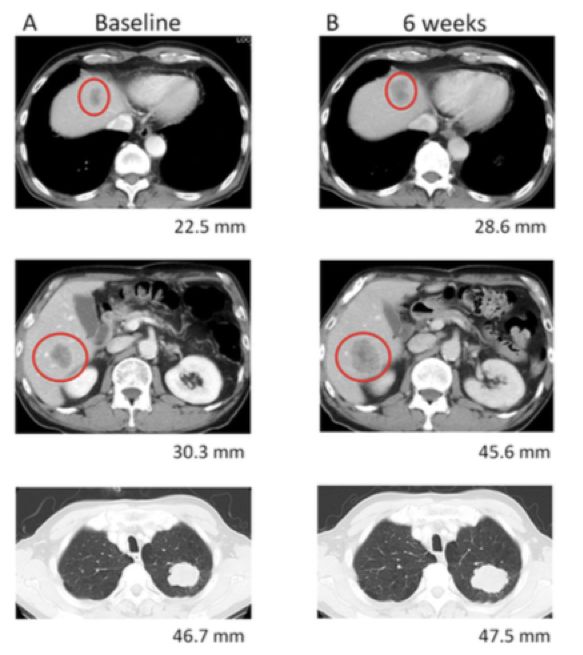

图1. 患者初诊(A)、纳武利尤单抗治疗6周(B)肝转移灶和肺原发灶的CT影像

图3. 患者初诊(A)、纳武利尤单抗治疗6周(B)、纳武利尤单抗治疗12周(C)肝转移灶和肺原发灶的CT影像

对于免疫治疗后病灶增大,但是血清CEA水平下降,患者症状及体征好转且耐受性良好的情况下需要综合考虑 ,排除假性进展可能,该类人群也可能是免疫治疗获益人群。该患者选择了继续使用纳武利尤单抗免疫治疗,12周后复查CT提示原发灶和转移灶均缩小,血清CEA持续下降,故该患者考虑为假性进展。